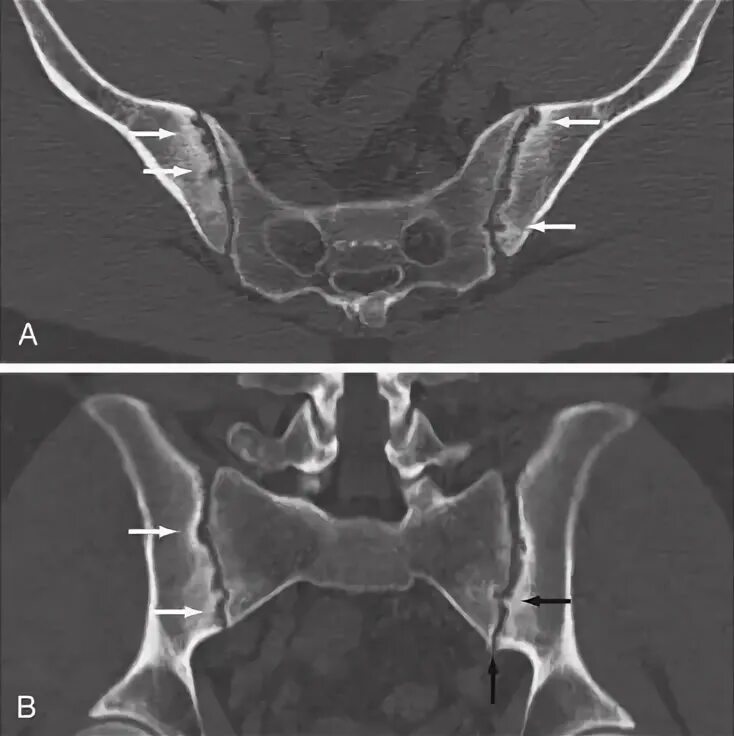

Сакроилеит на кт